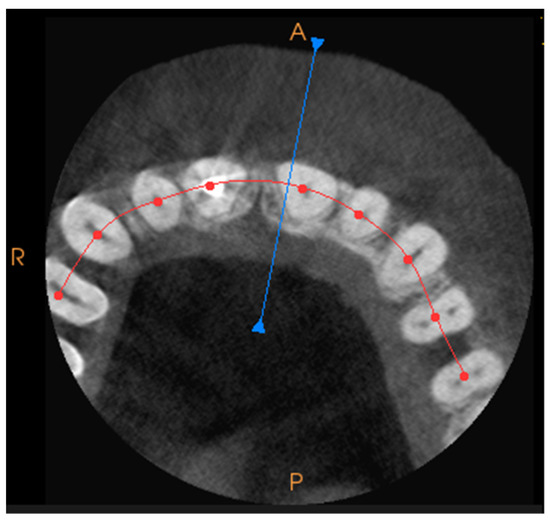

Prior to treatment as well as during the whole procedure, the analysis of computed tomography scans was performed. The opposite of a 2D X-ray, this is a procedure that requires time to carefully evaluate each plane. To obtain a precise radiological image, a pantographic curve should be drawn, as shown in Figure 1. The analysis of each of the resulting planes: transverse, longitudinal, and axial, can be carried out with an accuracy of 0.1 mm. Table 1 lists the items that are assessed pre-treatment on CBCT scans.

Figure 1. The CT scan of a tooth with a pantographic curve, with the blue line marking the angle and perspective for the front view, can be generated separately. The red line marks the pantographic curve.